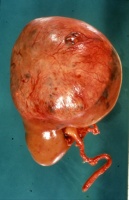

Makroskopisch zeigt der Tumor eine gelborange Farbe und ist durch Einblutungen und weißliche, Nekroseherde gesprenkelt. Außerdem finden sich Zysten von Millimeter- bis Centimeter-Größe (Abbildung 1). Auffällig häufig enthält das Nierentumorgewebe Kalzifizierungen. Zumeist ist der Tumor mehr oder weniger gekapselt und dadurch vom Nierenparenchym abgetrennt (s. Abbildungen Kasuistiken).